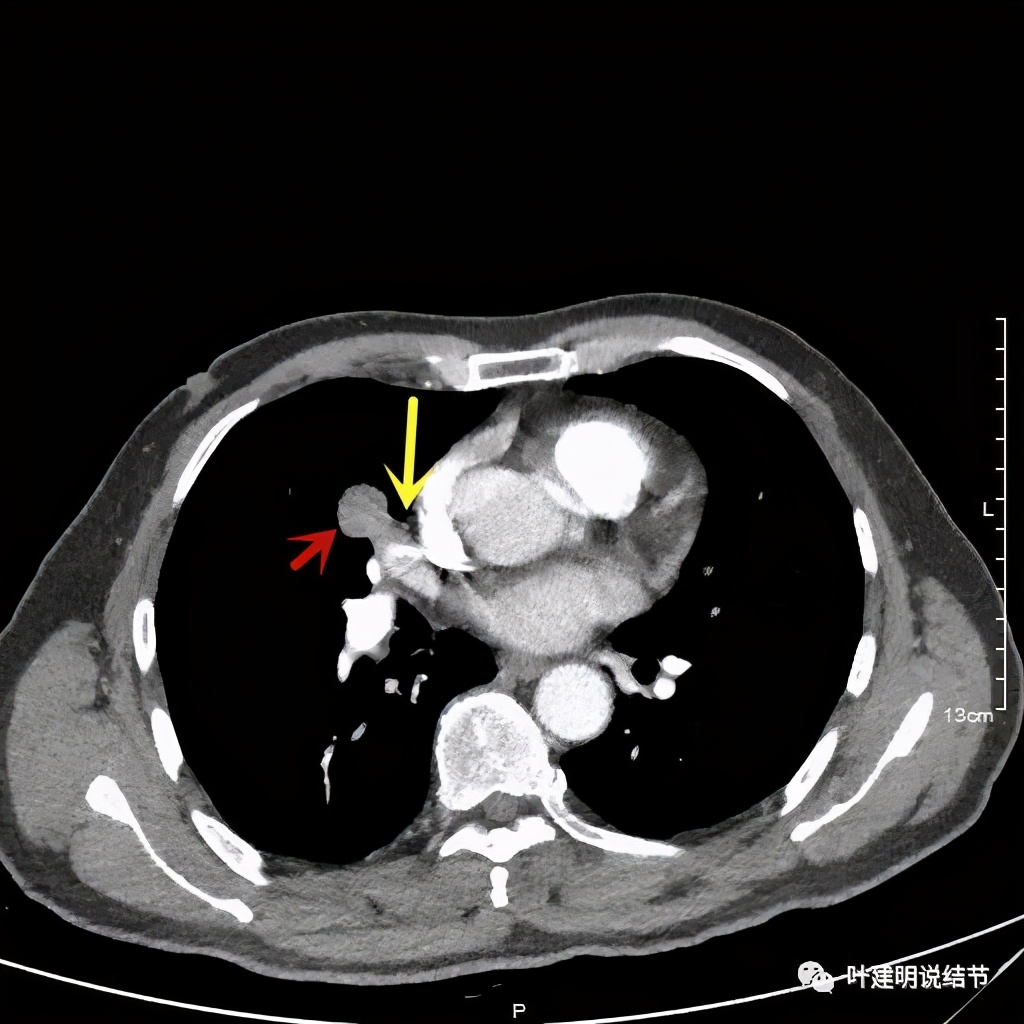

黄色箭头示病灶附近淋巴结或癌结节可能性大

上图示血管被病灶影响,似乎有侵犯

上图示血管在病灶内挤压变细